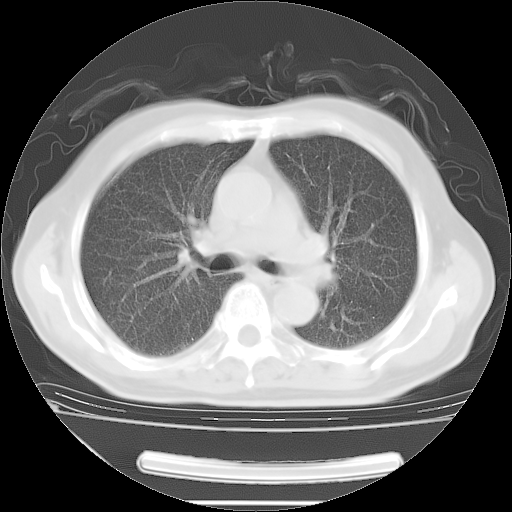

今天复查肺部CT,发现双肺广泛磨玻璃样改变。所以我把3月19日和5月9日相隔50天的肺部CT上传。请大家会诊。

2009年3月19日肺部CT片。

2009年3月19日肺部CT

大致读了系列胸部CT:纵隔窗无明显异常,肺窗:从4、27至今:主要是双肺中下野外带可见毛玻璃样改变,目前处于急性肺泡炎阶段,至于原因考虑1、结替组织或胶原血管性疾病所致?2、恶性疾病如恶组在肺部所致的表现或细支气管肺泡癌?3、药物或其它原因如肺蛋白沉着症所致肺泡炎目前不太可能?总之,明天就去请我院的呼吸科、感染科、血液科和临免专家会诊哈。